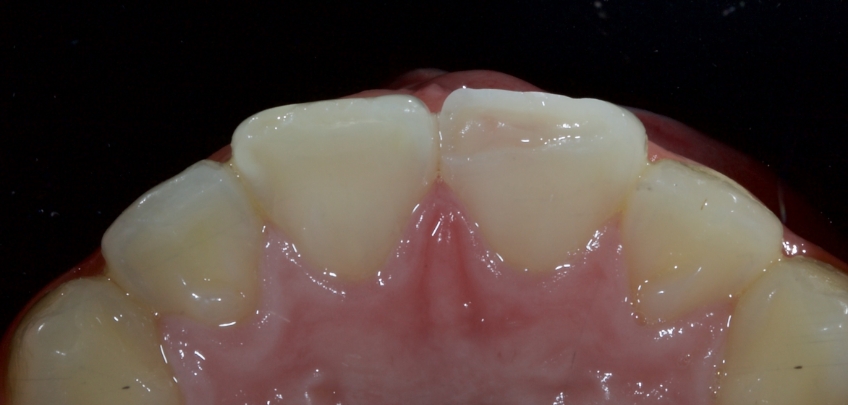

Case #1: Fragment Reattachment

Any biofilm and aprismatic enamel were removed from the tooth, and the fragment was fragmented with light hydro abrasion with 29-micron alumina at 2-3 bar pressure. The tooth and the fragment were etched with 37% phosphoric acid (Ultradent), and a fourth-generation dentin bonding agent (Kerr, OptiBond FL) was applied (the adhesive component was not light-cured).

The fragment was luted to the tooth with heated chromatic enamel shade composite (GC G-aenial A2 shade). The heater used was a Calset Warmer from Addent. The excess composite was cleaned with an interproximal carver from American Eagle and smoothed with a number three brush and modeling resin (Brush & Sculpt from Cosmedent).

The composite was heated because it gained lower viscosity to improve adaptation. Plus, heating increases the conversion of monomer to polymer, which improves the physical characteristics of the resin, such as flexural strength and wear resistance, according to research by Da Costa, Hilton, and Swift in 2011.

The resin was polymerized, and the oxygen-inhibited layer was removed by polymerization under glycerine.

The enamel fracture on 2.1 was untouched and will be managed in conjunction with esthetic management of the white hypo calcification at a later time.